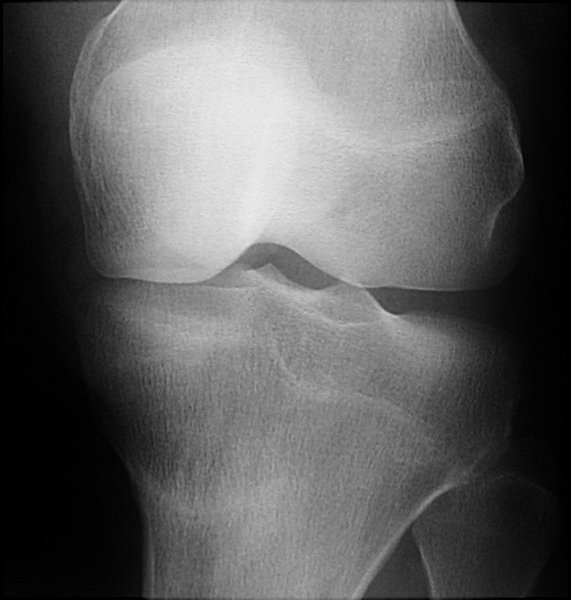

Return to Stress Fracture (Tibia)